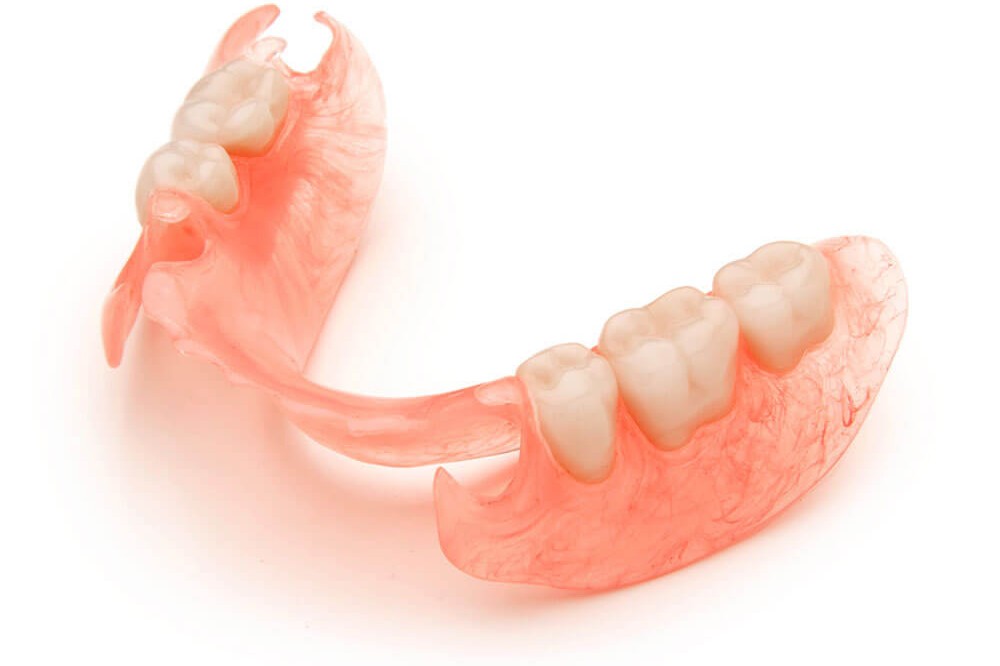

- Mantenitori di spazio